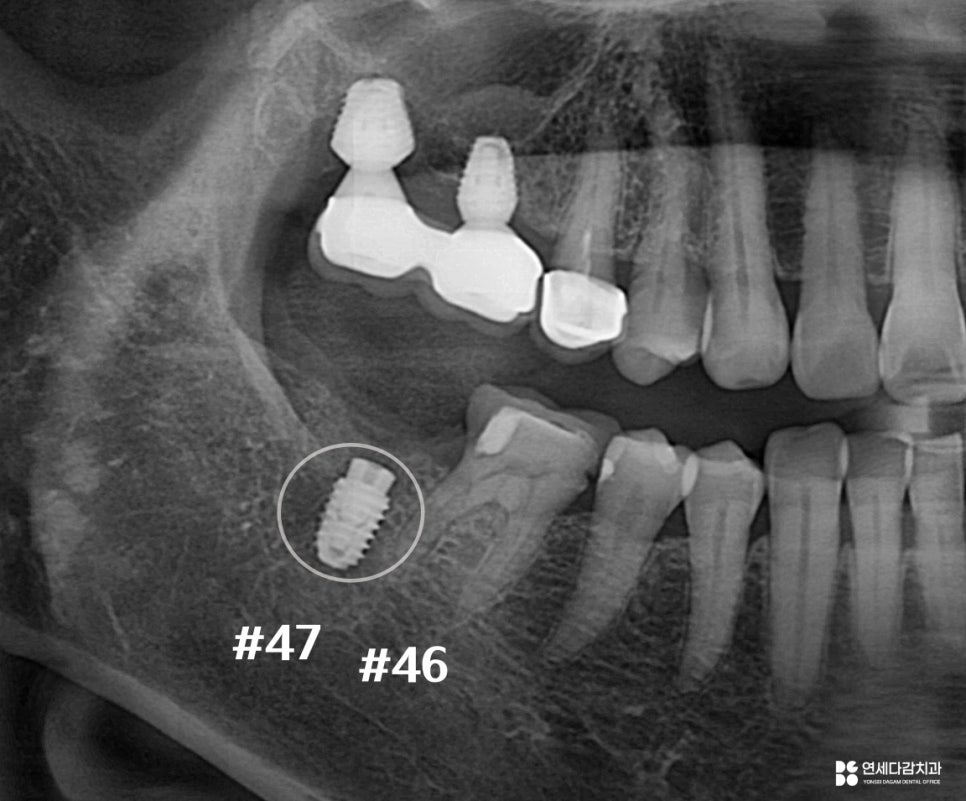

위아래 병변의 진행 정도를 살펴봤을 때,

47번은 이미 치근 부위로 확산되어 있습니다.

치근은 치조골 속에 위치하고 있어

병변에 접근하는 것이 매우 어렵습니다.

또한 치근이 손상되면 강도 자체가 저하되어,

저작압을 버티기 어려운 상태가 됩니다.

2025.11.12

이미 뿌리가 약해진 상태에서는

장기적인 유지를 기대하기 어렵고

결국 발치로 마무리되는 경우가 많습니다.

기능 회복을 위해 임플란트를 심은 모습입니다.